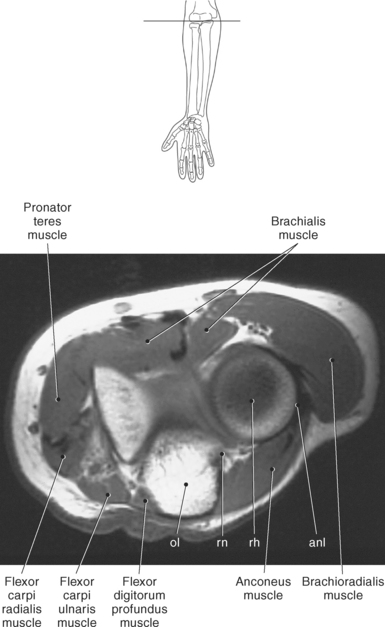

The elbow is a complex hinge-pivot joint created by the articulations of the humerus, radius, and ulna. All three articulations communicate with each other within a single joint capsule. The radius and ulna are the bones of the forearm, with the radius located on the lateral side. The radioulnar and radiohumeral articulations create the pivot joint that aids in supination and pronation of the elbow. The radiohumeral and ulnohumeral articulations form the hinge joint that allows for flexion and extension (Figures 9.70 through 9.73).

The distal portion of the humerus has two distinct prominences termed the medial and lateral condyles, with associated epicondyles, that provide attachment sites for tendons and ligaments (Figure 9.70). The medial epicondyle serves as the site of origin for the common flexor tendon, pronator teres muscle, and medial collateral ligament, whereas the lateral epicondyle serves as the attachment site for the common extensor tendon, supinator muscle, and lateral collateral ligament. Just lateral to the medial epicondyle along its posterior surface is a shallow groove containing the ulnar nerve. Two depressions located on the distal humerus are the anterior coronoid fossa and the deep posterior olecranon fossa. These depressions accommodate the coronoid and olecranon processes of the proximal ulna (Figures 9.70, 9.71, and 9.73). The distal humerus has two cartilage-covered articular surfaces—the capitellum and the trochlea for articulation with the radius and ulna (Figure 9.71). The lateral of the two surfaces is the capitellum, a rounded projection that articulates with the concave surface of the radial head. The trochlea is more medial and has the appearance of an hourglass if viewed in the horizontal plane. The shape of the trochlea helps keep the ulna in position during flexion between the distal humerus and proximal radius (Figure 9.73).

The radius is a long, slender bone with a proximal portion that consists of the radial head, neck, and tuberosity. The radial head has a flat cartilage-covered depression or fossa (fovea of the radius) that articulates with the capitellum of the humerus. In addition, the articular circumference of the radial head articulates against the radial notch of the ulna during supination and pronation. The radial head is attached to the body of the radius by the narrow radial neck. Located at the distal portion of the neck on the medial side of the radius is a roughened projection termed the radial tuberosity. The radial tuberosity serves as the attachment point for the biceps brachii muscle (Figures 9.72 through 9.74).

The ulna is located medial within the forearm. The proximal ulna consists of the olecranon and coronoid processes and the trochlear and radial notches. The superficial dorsal surface is formed by the hook-shaped olecranon process, which is the attachment site for the triceps brachii. The trochlear notch is a half-moon-shaped concave articular surface that curves around the trochlea of the humerus. This articulation allows for flexion and extension of the elbow. Located on the anterior portion of the distal end of the trochlear notch is a small beaklike process called the coronoid process. Just distal and lateral to the coronoid process is a flattened depression called the radial notch. It is covered by articular cartilage for articulation with the radial head. Immediately distal to the coronoid process is a roughened bony surface termed the ulnar tuberosity. The tendon of the brachialis muscle inserts on both the coronoid process and the ulnar tuberosity (Figures 9.72, 9.73, 9.75, and 9.76).